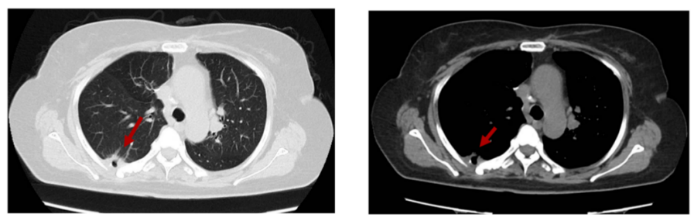

2019-8-15 复查右下肺胸膜下软组织结节较前增大,2019-8-30 程志强教授于CT引导下行右下肺胸膜转移氩氦刀冷冻术。术后2019-9 至今,口服瑞戈非尼80-120mg qd d1-21,q28d,靶向治疗。期间根据患者不良反应分级多次进行靶向药物剂量调整。并辨证给予口服中药,针对靶向治疗不良反应,如手足皮肤反应等,给予外用中药对症治疗。

图4 CT引导下右下肺胸膜转移瘤氩氦刀冷冻消融术

图5 氩氦刀术后规律口服瑞戈非尼,定期随访,疾病稳定

2022-7-23 随访复查胸腹CT平扫示右下肺胸膜下小片实变影伴空洞,较前片变化不大。评效SD。

图6 2022-7末次随访:右下肺胸膜下小片实变影伴空洞